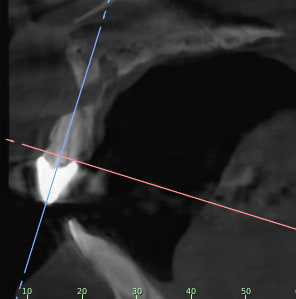

Je rajoutes quelques coupes et une rétro... C'est vraiment un massacre à la tronçonneuse!

24/04/2019 à 15h19

D'autres coupes et une rétro